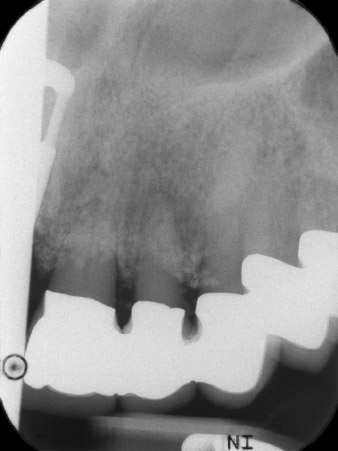

първоначални рентгенографски резултати

Фиг. 1: Първоначалните рентгенографски резултати показват възстановяване с шинирана корона, изискваща смяна. Когато тя е премахната, зъби 21 и 22 са били неумишлено екстрахирани заедно с нея.

Рентгеновата снимка показа хоризонтална загуба на кост около зъби 21 и 22 (Фиг. 1). Когато короната е отстранена, тези зъби са били неумишлено екстрахирани с нея.